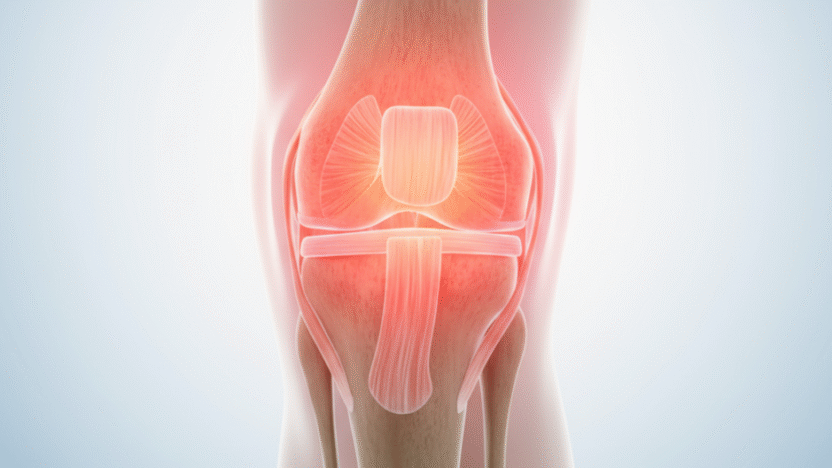

A joint is the connection point between two or more bones, allowing smooth and flexible movement. These joints are cushioned by cartilage, lubricated by synovial fluid, and supported by ligaments, tendons, and muscles. When any of these components become inflamed, worn down, or damaged, pain occurs.

Sprains, strains, fractures, and dislocations can all result in acute or chronic joint pain. Even after healing, residual inflammation or scar tissue can limit motion and cause discomfort.

3) Tendinitis and Bursitis

Inflammation of the tendons (tendinitis) or bursae (small fluid-filled sacs that cushion joints) can lead to pain, especially in the shoulders, elbows, knees, and hips.